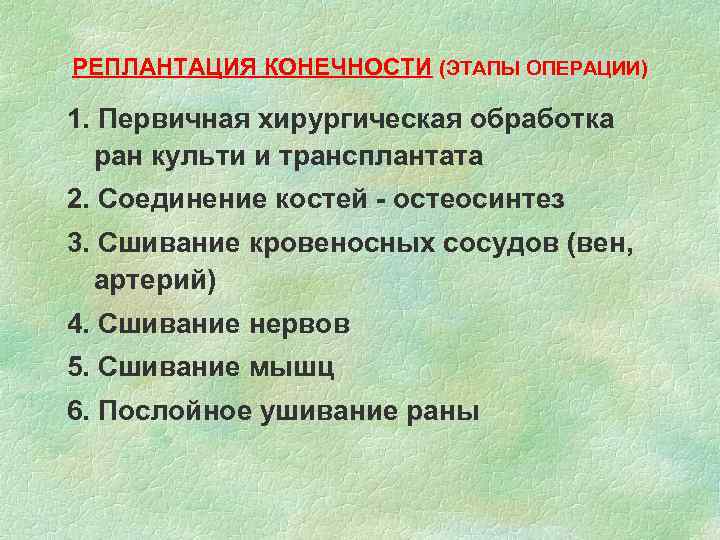

Реплантация зуба: Этапы и особенности операции